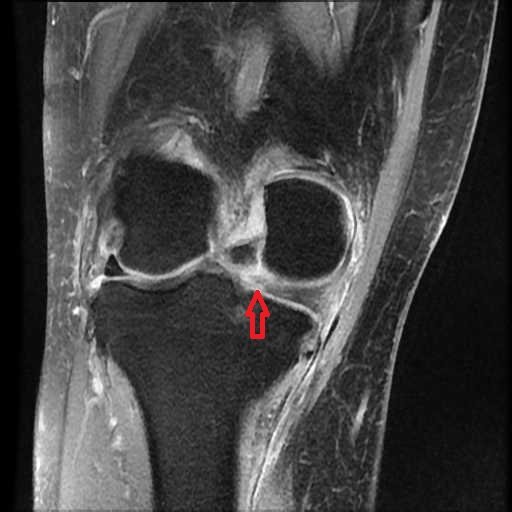

以下はMMPRT(赤矢印)のMRI像です